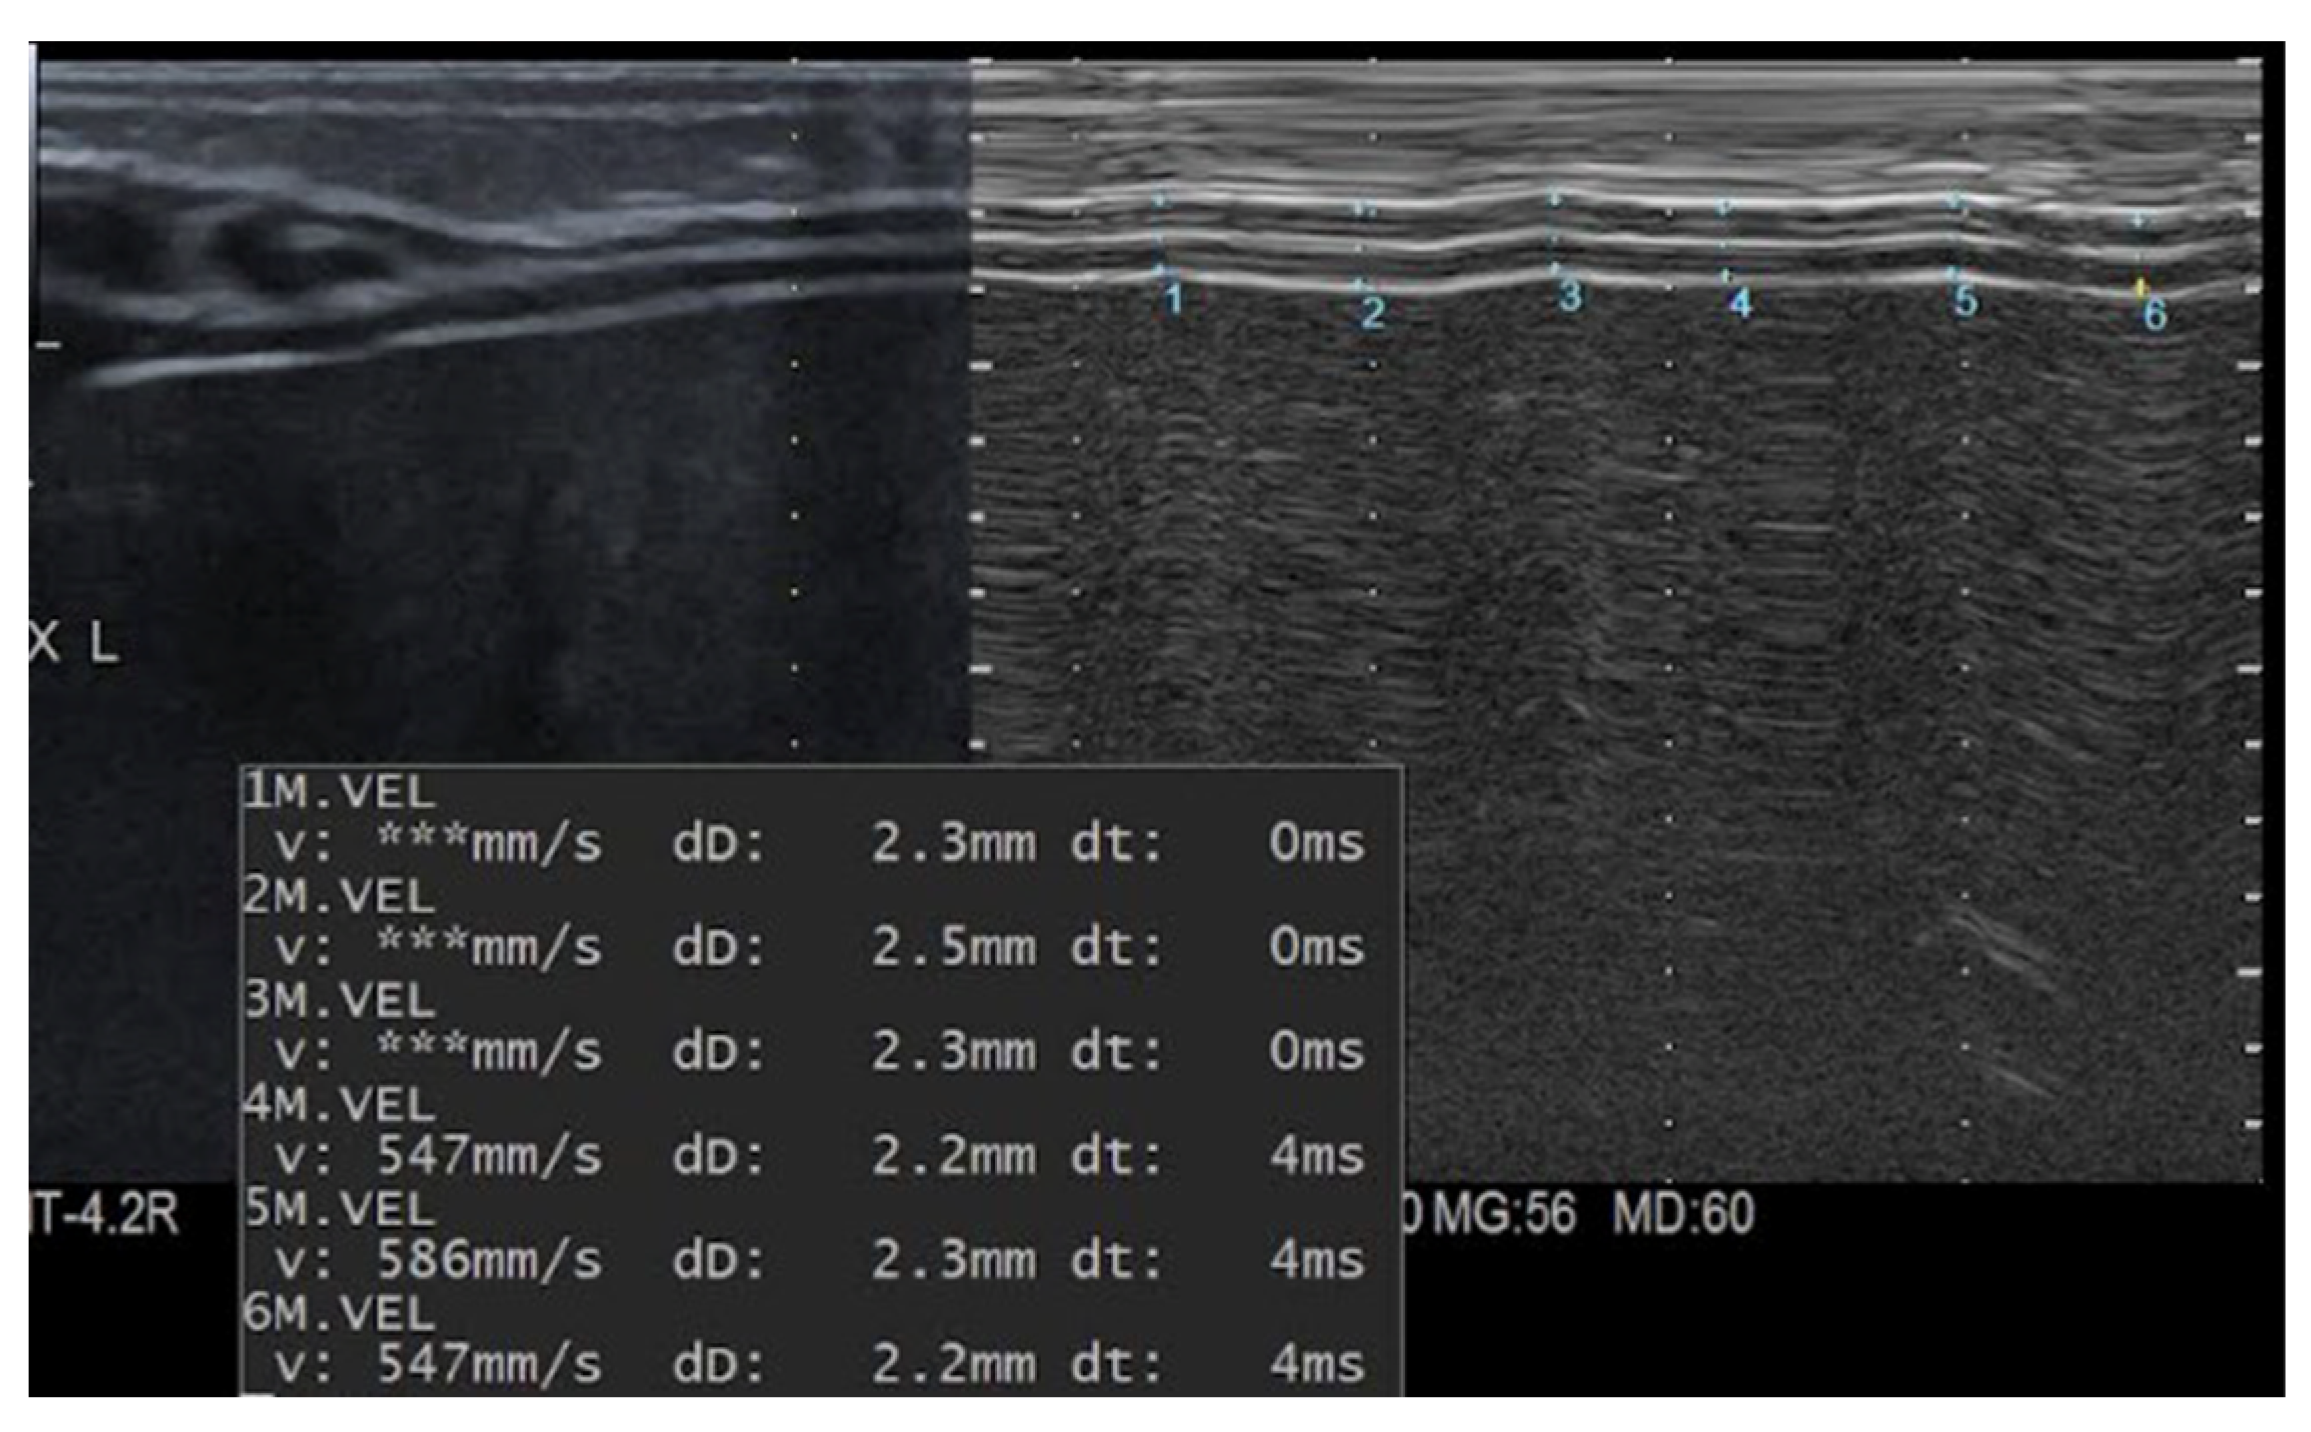

2.1. Ultrasound Equipment and Technique

2.2. Assessment of Reproducibility